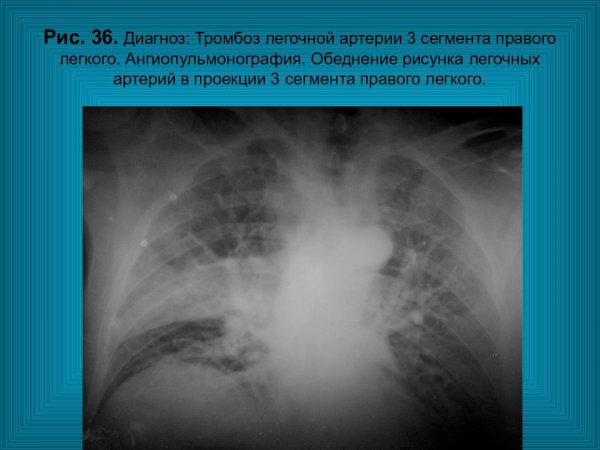

Ангиопульмонография Тэла